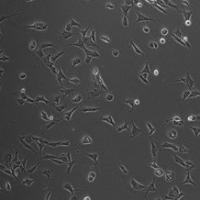

图1.心房心肌细胞

图2.心室心肌细胞